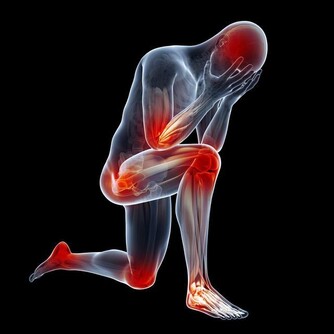

我們可以從一個人的聲音辨別一個人,同樣我們也可以從一個人的走路姿勢來辨別一個人,因為我們每個人的走路姿勢、速度、手腳擺動幅度、晃動的角度、身體部位移動的特徵皆不相同。但你知道嗎,從一個人的鞋底磨痕也能看出這個人的身體狀況。下面小編就這個話題跟大家囉嗦幾句,為了大家的健康請耐心讀完下文。

你知道嗎?鞋底的磨損狀況反映了身體的疾病狀況。鞋底內側磨損較多,可能是小腿向外彎曲,有形成X腿的危險。鞋跟內側磨損的人要警惕佝僂病、脛骨發育不全;而鞋底外側磨損較多,則表明小腿脛骨向內翻,有形成O形腿或「內八字」的風險。骨科醫生表示,如果左右腳磨損程度對稱,也不必太在意。

正常人步行,呈輕度外八字形,鞋跟都會有或多或少的磨損,磨損位置集中於後跟外側,且對稱。通常情況下,如果新買的鞋子,半年磨掉20%以內,一般視為正常的。如果3個月內就磨損掉20%~30%,就不是走路姿勢的問題了,基本上可以判斷是身體出了問題。常見的原因,有髖關節疾病,像先天性髖關節半脫位,髖關節發育不良,脊柱側彎等。

中山二院骨科黃醫生認為,腰椎骨的變形未必能從走路姿勢中看出來。有些人,腰椎骨本身沒問題,可能踝骨和腳跟骨本身長歪了,這些都會在鞋底磨損上有所體現。他分析說,鞋底磨損反映的常見病是內八字和外八字。內八字走路容易使更多的壓力積聚在腳外側,增大了關節的壓力,時間久了會形成O形腿。

外八字走路,久而久之膝蓋也會外移,雙腿變成X型。這些人上了歲數就會出現關節痛疼,加速關節老化。林華表示,有很少的一部分人,鞋跟內側磨得厲害,通常這些人走路姿勢呈內八字形,需要到骨科矯正。琥珀帶3個月,身上的疾病減輕了,因為內八字背後還藏著一些疾病。臨床上,一些佝僂病、脛骨發育有問題的患者走路常常是內八字,除了「O形腿」,還可表現為「X形腿」。